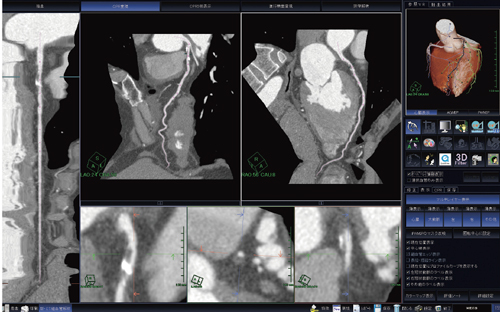

また,冠動脈が自動認識された状態でソフトウェアは立ち上がってくるので,CPRやstretched-CPRの画像を確認しながら,対象となる冠動脈に名前をつけるだけで作業は終了となる。しかしながら,冠動脈解析はソフトウェアが自動化されても必要に応じて修正を行わなくてはならない。なぜならば,CPRでは冠動脈の中心を通っていないと偽画像を作成してしまうからである。ソフトウェアの自動化は,画像作成を行う上でとても便利な機能であるが,あくまで画像作成サポート機能であるため,画像提供を行う際にはしっかりと確認を行わなくてはならないことを常に念頭におきながら画像作成および提供を行うようにしている(図2)。しかし,“新・CT細血管解析”における冠動脈の認識率は,従来のソフトウェアと比較して格段に高くなり,画像作成時の十分なサポートを担っていると言える。

図2 冠動脈CPR表示画面